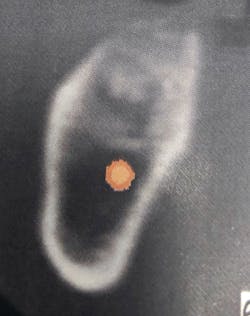

Although there are many types of grafting products commercially available, choosing the right one may be difficult. An ideal bone graft substitute should be biomechanically stable; able to degrade within an appropriate time frame; exhibit osteoconductive, osteogenic, and osteoinductive properties; and provide a favorable environment for invading blood vessels and bone-forming cells.10